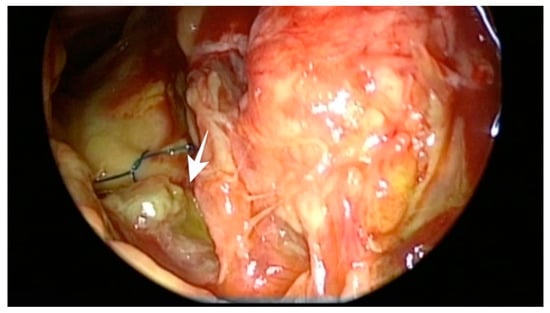

2.2. Surgical Approach and Reconstruction Technique